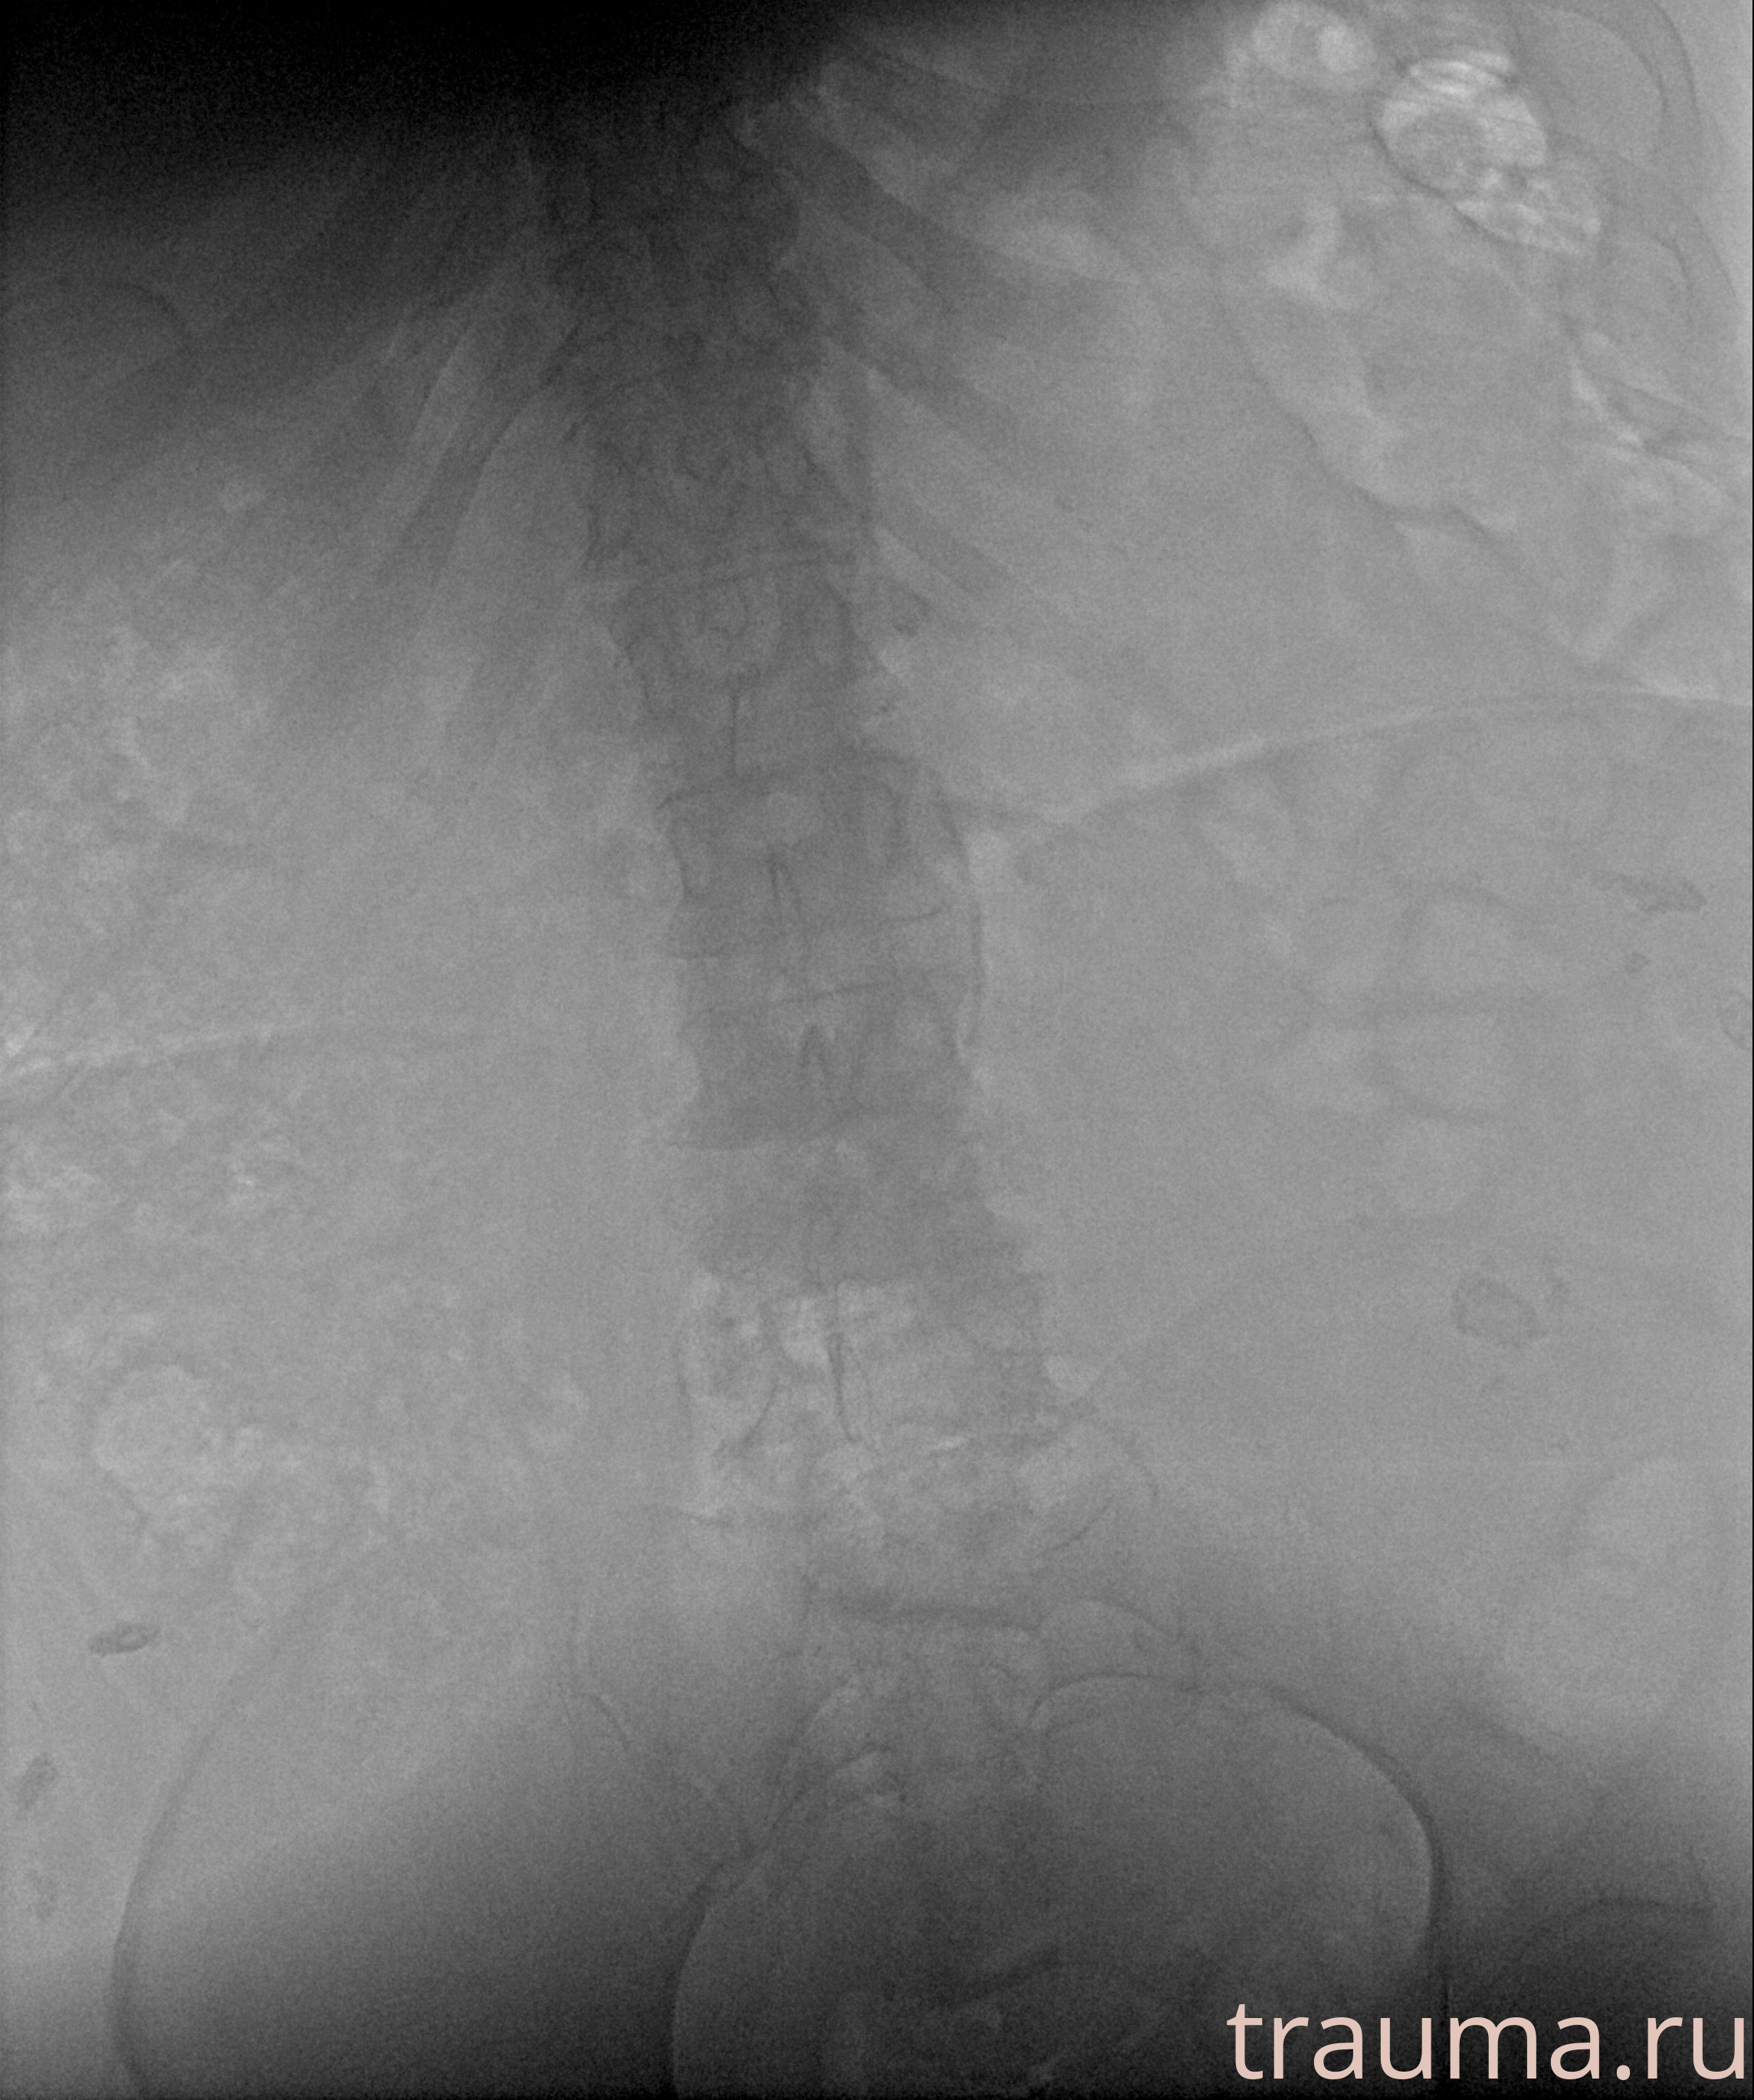

Рентген на дому: по вашему адресу приезжает врач-рентгенолог, травматолог-ортопед с мобильным рентгеновским аппаратом, проводит диагностику травмы или заболевания, делает необходимые рентгенограммы, дает рекомендации по дальнейшему лечению. Получить качественные снимки в домашних условиях возможно благодаря уникальной методике, разработанной МосРентген Центром для института  Склифосовского